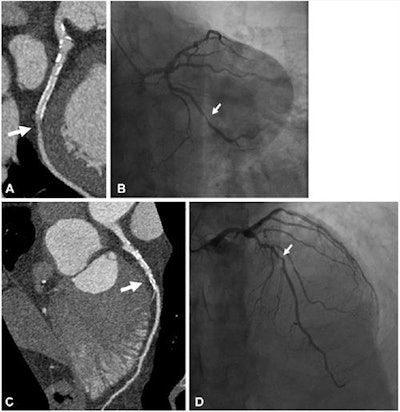

Each patient underwent ultrahigh-resolution CT within 30 days before cardiac catheterization; the researchers compared image noise levels and diagnostic confidence and image quality (the latter two measures ranked on a scale of 1 to 5, with 5 indicating highest quality) from these images to reconstructed images simulating conventional CT exams. They also compared UHR-CT and angiography performance for assessing stenosis in the major heart arteries and the left main artery.

UHR-CT produced more image noise than conventional CT image reconstruction (50.9 versus 19.5), but even so, diagnostic confidence and image quality scores were high (4.3 and 4.1), the researchers found. When they compared the performance of ultrahigh-resolution CT to the gold standard of invasive angiography for evaluating stenosis, they found a sensitivity rate of 86% and specificity of 88%.